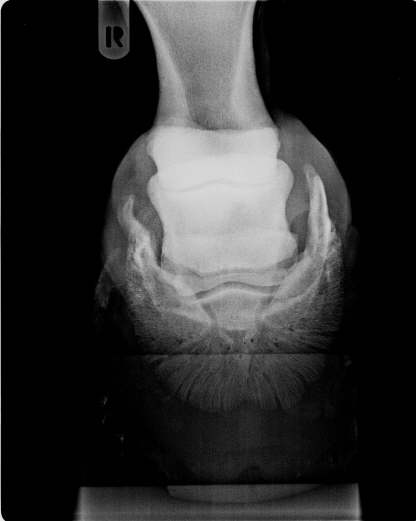

Oxspringaufnahme

Starke Hufknorpelverknöcherng